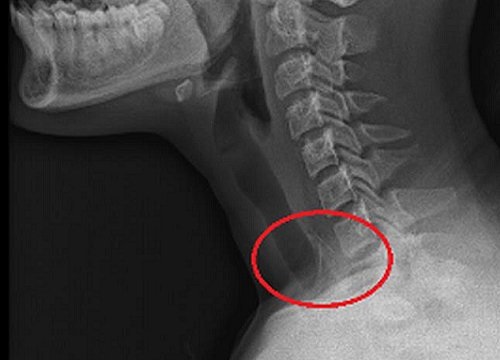

Hóc xương gà có thể bị thủng thực quản như người phụ nữ ở TP. HCM này. Nữ bệnh nhân 33 tuổi cấp cứu tại Bệnh viện Trưng Vương (TP HCM) trong tình trạng đau vùng cổ, nuốt nghẹn sau khi hóc xương gà.

Bệnh nhân cho biết không may nuốt phải xương gà trong lúc vừa ăn phở vừa nói chuyện. Sau đó vùng cổ đau nhiều, chị ăn thêm ổi và lê với mong muốn đẩy dị vật xuống nhưng càng ăn càng thấy đau, nuốt nghẹn nên vào viện cấp cứu.

Các bác sĩ Bệnh viện Trưng Vương nội soi, phát hiện dị vật cắm sâu 1/3 trên thực quản bệnh nhân. Kíp nội soi đã lấy thành công chiếc xương gà ra ngoài. Tại vị trí mắc xương, thực quản bị rách dài khoảng 5 mm và khá sâu, có khả năng thủng thực quản đoạn trên.

Bác sĩ Trịnh Quốc Minh, Trưởng Khoa Ngoại Lồng ngực Mạch máu Thần kinh cho biết sau khi nội soi, bệnh nhân chụp CT Scanner vùng cổ, phát hiện thực quản bị thủng 1/3 trên như dự liệu. Bệnh nhân được cho nhập viện, điều trị bằng cách nhịn ăn, uống, dịch truyền nuôi dưỡng và sử dụng kháng sinh mạnh, phổ rộng nhằm ngăn ngừa nhiễm trùng.

Sau 4 ngày bệnh nhân được chụp CT Scanner kiểm tra vùng cổ, kết quả không phát hiện áp xe quanh cổ, khí cạnh khí quản và thực quản đã giảm. Nội soi kiểm tra thấy lỗ thủng lành dần, không cần sử dụng kẹp để đóng lỗ thủng. Bệnh nhân được tiếp tục theo dõi và điều trị nội khoa cho đến khi xuất viện.

Theo bác sĩ Minh, đây là trường họp xử trí ban đầu không đúng cách khi bị hóc dị vật xương ở hầu, họng, thực quản trong lúc ăn uống. Trong khi ăn, cần nhai kỹ và hạn chế nói lớn tiếng. Khi có dấu hiệu mắc dị vật cần ngưng ăn và không cố sử dụng các loại thức ăn như cơm nguội, chuối, trái cây, rau… để cố gắng đẩy dị vật xuống dạ dày. Cần đến các bệnh viện có đủ phương tiện để nội soi lấy dị vật.